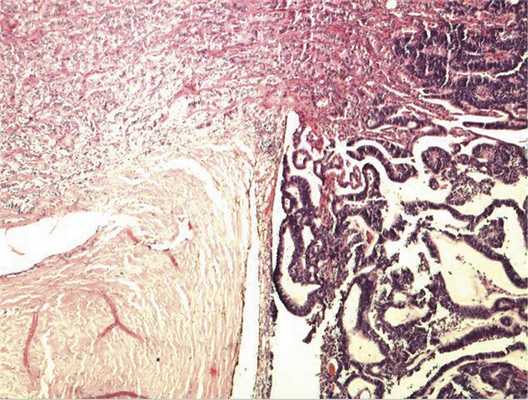

Патоморфологическое исследование. При морфологическом исследовании кусочка новообразования из боковой колодки выявлена опухоль, состоящая из кубических эпителиальных клеток, которые формировали единичные розетковидные структуры и небольшие участки солидного роста. Поставлен предварительный диагноз — недифференцированная ретинобластома без опухолевых комплексов в дистальном отрезке зрительного нерва. Далее при изучении срезов всего глазного яблока выявлен большой опухолевый узел в центральных отделах глазного дна, тесно связанный со зрительным нервом. Узел состоял преимущественно из трубчатых и сетчатых структур, розеток, ленточных образований, что придавало опухоли местами вид «кружева» (рис. 3).

Рис. 3. Часть узла опухоли снаружи от ДЗН, имеющая вид «кружева». Окраска гематоксилином и эозином. Ув. 100.